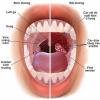

Thiếu máu não là tình trạng máu lưu thông lên não kém dẫn đến không cung cấp đủ dinh dưỡng và oxy cần thiết cho các hoạt động của não

![]() Dấu hiệu: Đau đầu, hoa mắt, chóng mặt, mất ngủ...

Dấu hiệu: Đau đầu, hoa mắt, chóng mặt, mất ngủ...